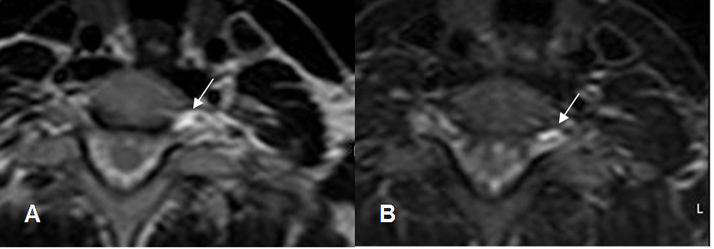

Fig 7. Neuropraxia.

A: RM axial en T2y B: RM axial en STIR. Presencia de líquido rodeando la raíz izquierda, después del agujero de conjunción, posterior a un accidente con hiperextensión del hombro.